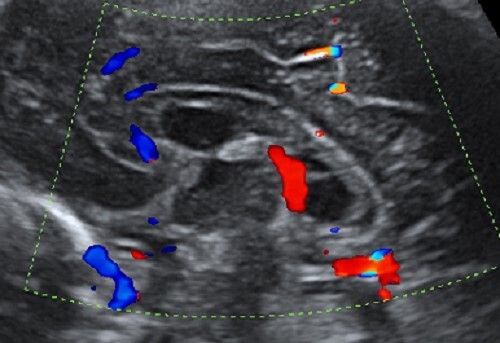

Neonatology Cavum Vergae Image